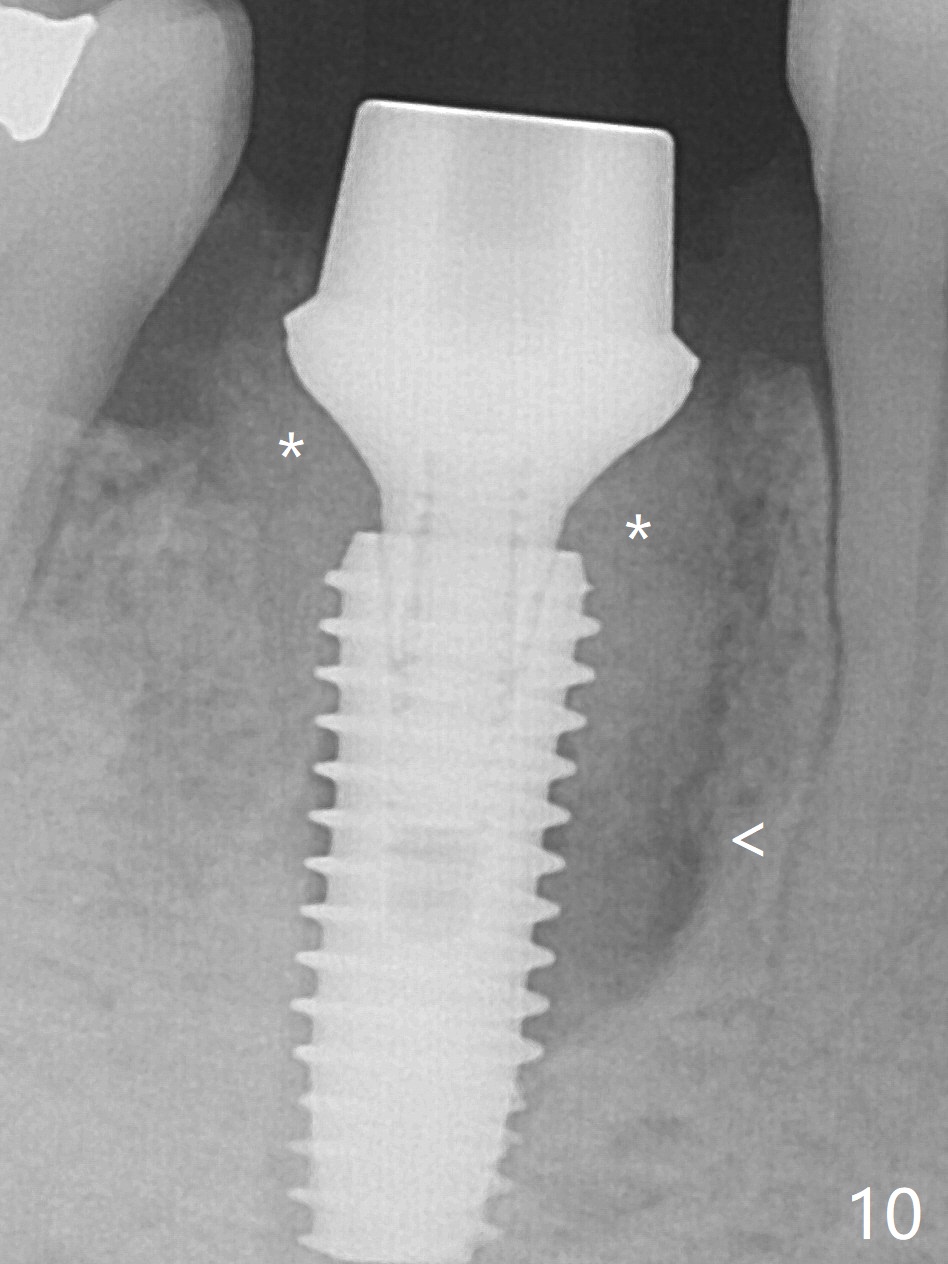

Preop oral Amoxicillin seems to be associated with reduction in the buccal and lingual (Fig.3 arrow) fistulae at #30, but there is mesiobuccal swelling (Fig.1 *) with 7 mm pocket (Fig.2). Osteotomy is initiated in the middle of the septum (Fig.3-5 S). As the osteotomy increases, it shifts mesially (Fig.6 arrow). Guided surgery is able to reduce shifting. A 5x13 mm implant is not seated completely (Fig.7) apparently due to osteotomy shifting. After removal of the bone from the osteotomy distally, the implant remains unseated with lower torque value (Fig.8). Following reuse of the 4.3 mm drill deeper by 1-2 mm, the implant is seated to a satisfactory depth (Fig.9 with increase in torque to 50 Ncm) with placement of Vera Graft (*) and a 7.5x4(3) mm abutment. After a second round of allograft placement (Fig.10 *), the implant is found to be 4 mm from the IAC. At the later stage of osteotomy, the coronal end of the septum is destroyed with loss of osteotomy depth landmark. It is apparent that the soft tissue landmark may be more reliable. The implant threads appear to be covered by the bone graft 3.5 months postop (Fig.11). The abutment is changed to 6.5x5(3) mm one before impression with minor margin prep. The bone density seems to increase 5 months postop, i.e., immediately post cementation (Fig.12) and 10 months postop (5 months post cementation (after retightening abutment), Fig.13 (*)). Periimplantitis develops mesiobuccally, consistent with bone loss 1 year 7 months post cementation (Fig.14 *); the implant seems to have been buccally placed. Bone graft is necessary with PRF or GEM21S if the vein is small and 6-month membrane with a hole around a 7.5x4(4) cemented abutment for easy wound closure. Take 5x5 CM CBCT to determine which wall has defect, buccal or lingual. Check mesial contact. If so, remove the crown, reseat the abutment (possible incomplete seating) and re-impress after bone graft.